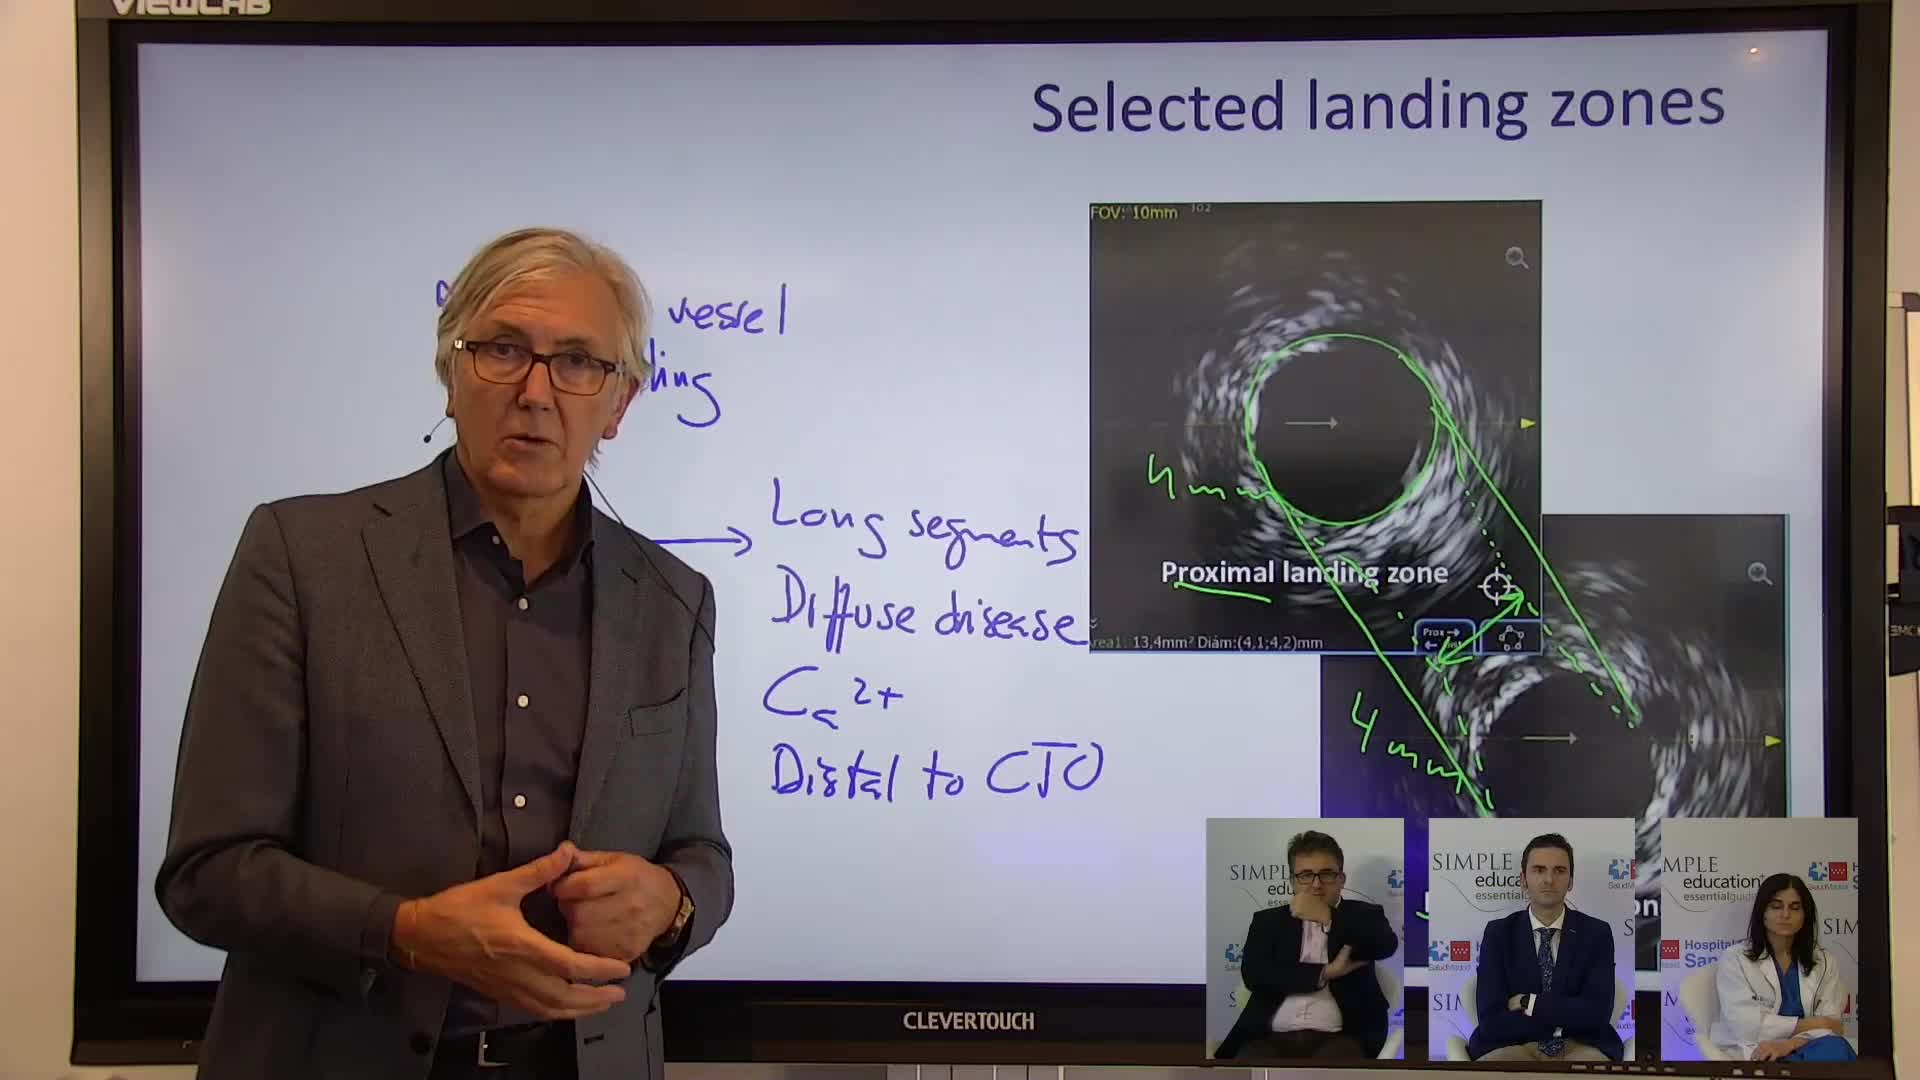

Complex PCI eCourse Madrid 26th October 2020

Complex PCI eCourse Madrid 27th October 2020

Coronary Bifurcations: An Update on Diagnosis, PCI planning and Imaging and PhysiologyGuidance - Dr Dejan Milasinovic